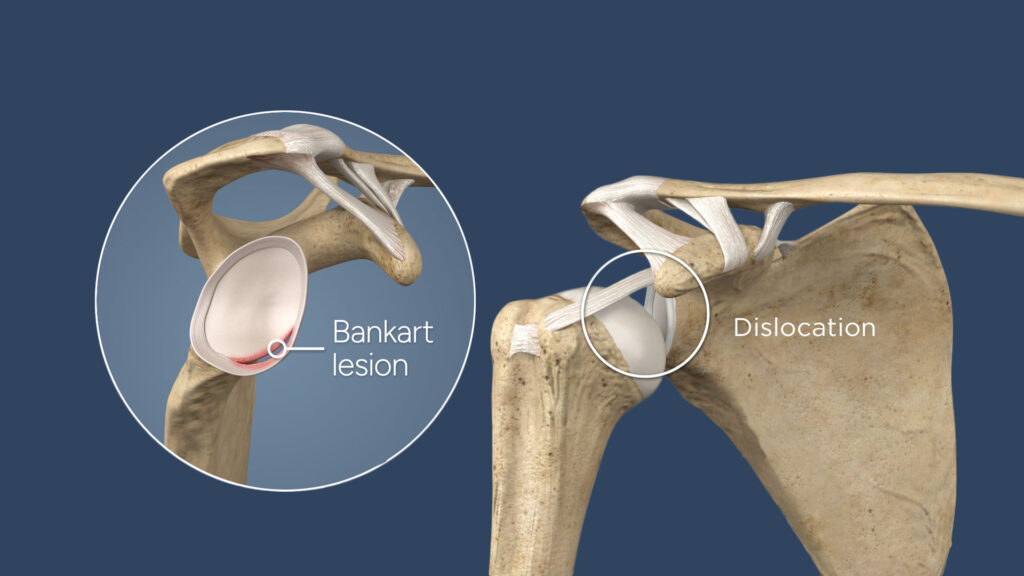

And because my body apparently doesn’t do anything small, it wasn’t just a dislocation. I had something called a Hill-Sachs lesion which is a fancy way of saying a chunk of bone got knocked out of place and my labrum was torn with the guys in the white coats call a Bankhart Lesion. I had to google what a labrum even was.